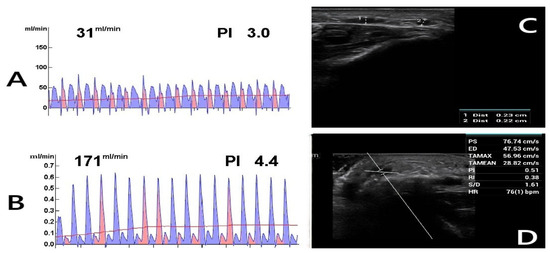

Postoperative DUS measurements revealed significantly higher AVF blood flow rates in males compared to females, as determined by the Brunner–Munzel test. At the fourth week, females had a 76.8% probability (95% CI: 0.68–0.85; p < 0.001) of having lower blood flow than males. While blood flow increased in both sexes by the sixth week, the improvement was more pronounced in males (mean difference: 255 mL/min for males vs. 199 mL/min for females). Consequently, the probability of females with lower blood flow further increased to 80.4% (95% CI: 0.71–0.89; p < 0.001) (Figure 2A–D).

Figure 2.

Postoperative Doppler ultrasound (DUS) assessment. The figure shows the postoperative evaluations of a 62-year-old diabetic female patient who continues to smoke. (A) TTFM measurement of the radial artery before anastomosis. (B) TTFM measurement of the radiocephalic fistula after anastomosis. (C) Fourth-week DUS examination reveals inadequate AVF maturation with a vein diameter of 0.23 cm (1), suggesting insufficient development. (2: Radial artery). (D) DUS parameters were measured as follows: PS (Peak Systolic Velocity): 76.74 cm/s, ED (End-Diastolic Velocity): 47.53 cm/s, TAMAX (Time-Averaged Maximum Velocity): 56.96 cm/s, TAMEAN (Time-Averaged Mean Velocity): 28.82 cm/s, PI (Pulsatility Index): 0.51, RI (Resistive Index): 0.38, S/D (Systolic/Diastolic Ratio): 1.61, HR (Heart Rate): 76 bpm. Blood flow (Q) was calculated using Q = TAMEAN × A × 60 [22], where A represents the vessel cross-sectional area. Given a fistula vein diameter of 0.23 cm, the calculated blood flow was 71.84 mL/min, indicating inadequate flow.